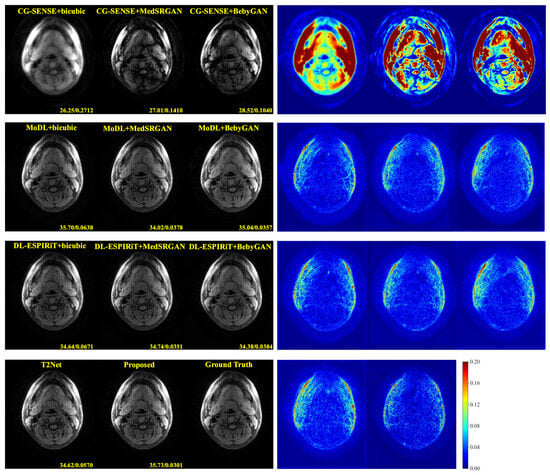

For a more intuitive comparison, we provide visual comparisons for each method. In Figure 5 and Figure 6, we illustrate the axial and sagittal views of the 2D brain dataset, respectively. In Figure 7 and Figure 8, we display the brain image and neck image of the 3D VWI dataset. For each method, we show the restorations along with the corresponding error maps. The images are placed on the left, the error maps on the right, and the PSNR and LPIPS metrics of each image are shown at the bottom right corner. From the error maps, it is evident that our proposed method consistently produces high-quality results with improved visual fidelity and better retention of structural information compared to the other methods.

Figure 7. Visual comparison of each method for a brain image in the VWI dataset.